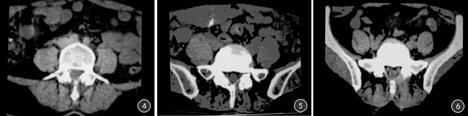

手术均在德国鲁道夫(Rudolf)椎间盘镜系统下完成,全套设备包括显示系统、镜头及光纤、手术通道及特殊手术器械等。A组:完成常规MED手术,术中对黄韧带实行完全切除。B组:与常规MED的不同之处在于对黄韧带的干预方式上的差异。显露好黄韧带后,从其外侧方着手,Kerrison咬骨钳酌情咬除部分上位椎的椎板下缘、关节突的内侧缘以及附着的黄韧带,小刮匙由椎板间隙的外下方向内上方剥离浅层黄韧带;如果黄韧带较厚,以致牵开、显露困难且难以判断神经根是否彻底减压,则咬除浅层黄韧带,保留深层黄韧带。依次游离深层黄韧带的近端、远端及外侧附着缘,使深层黄韧带呈上、下、外侧缘剥离的瓣状结构。摘除突出的椎间盘组织后,松开牵开器,黄韧带可完全覆盖椎板间隙或与周围组织间可留有1个1~2 mm的细小狭缝[3]。见图1、图2。4 ℃生理盐水冲洗伤口(硬膜囊破裂患者只用常温生理盐水冲洗),探查无活动性出血,拔出工作通道,留置橡皮引流卷1枚,缝合腰骶筋膜,关闭切口。